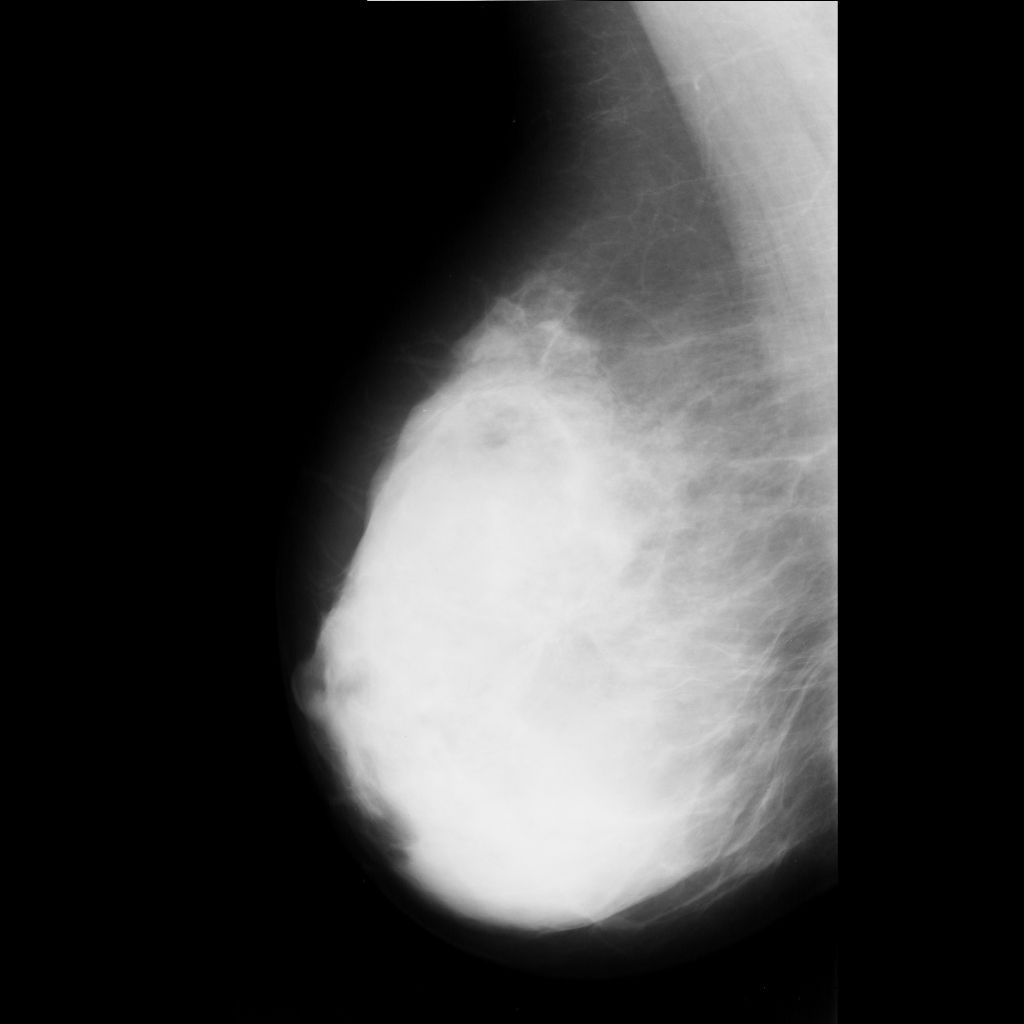

benign